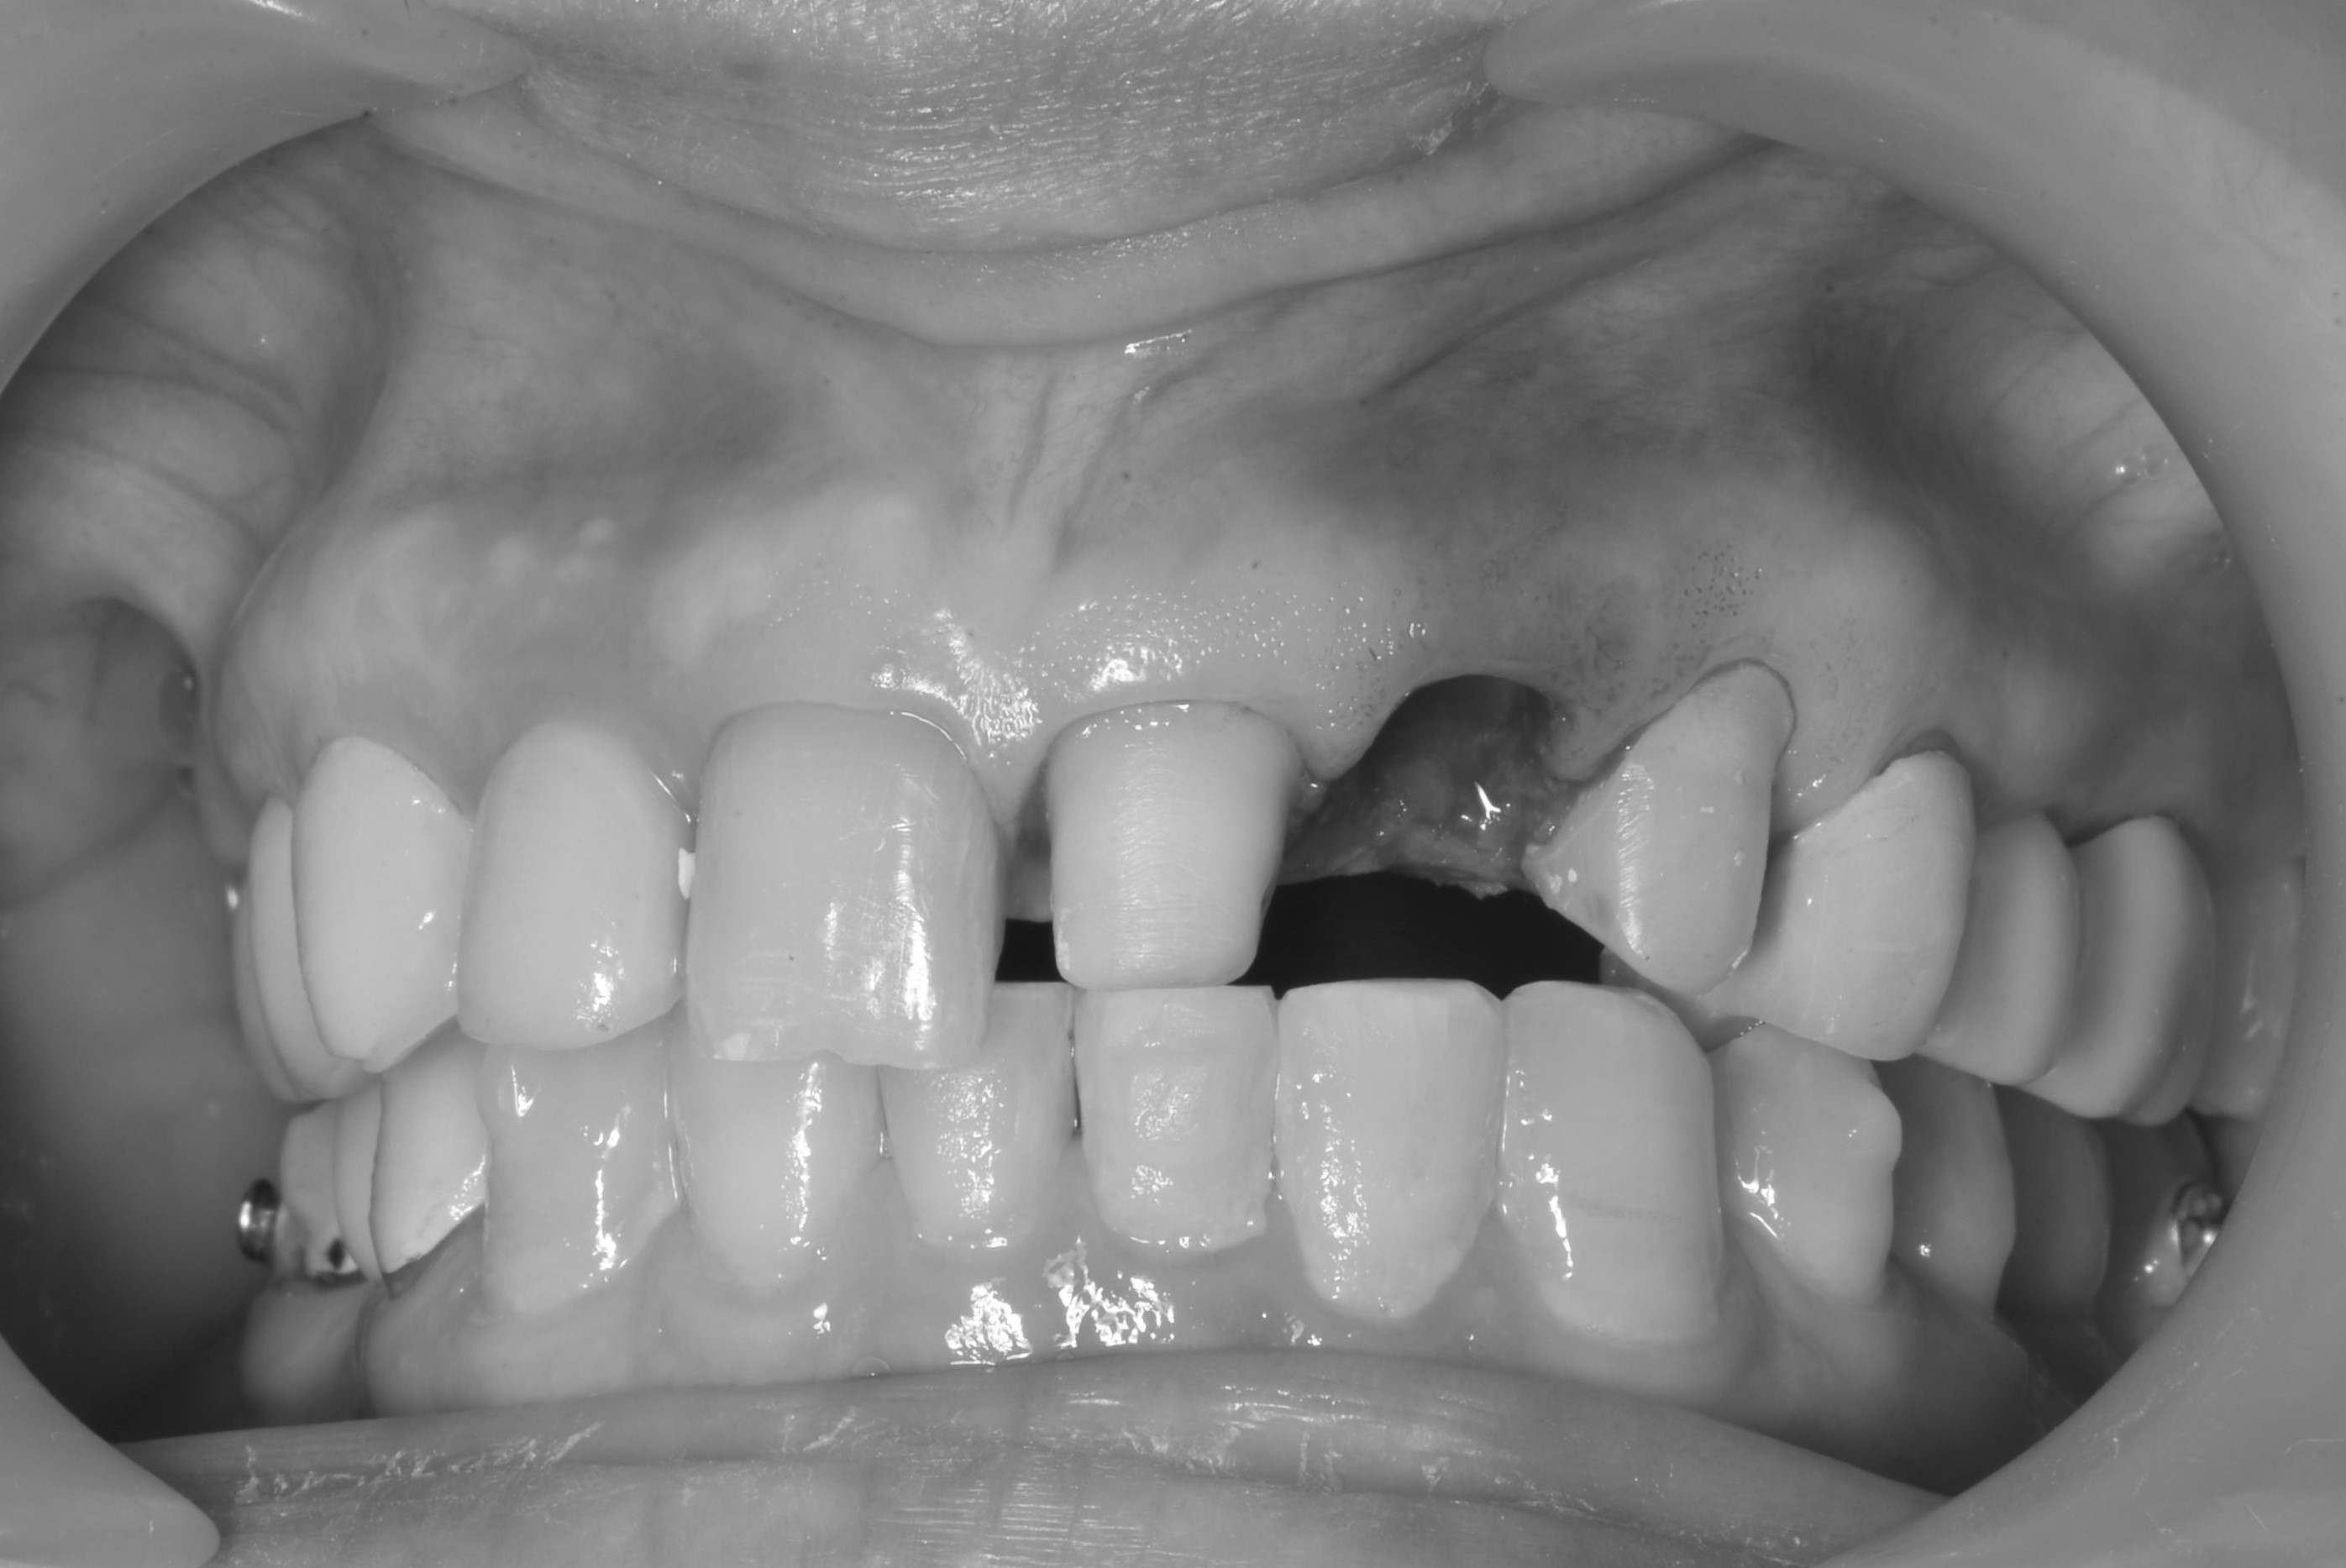

立即式植牙(即拔即種)